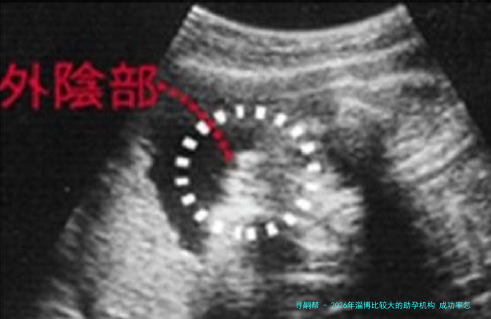

下列表格汇总了2026年淄博地域主要助孕机构的关键信息,供您参考。